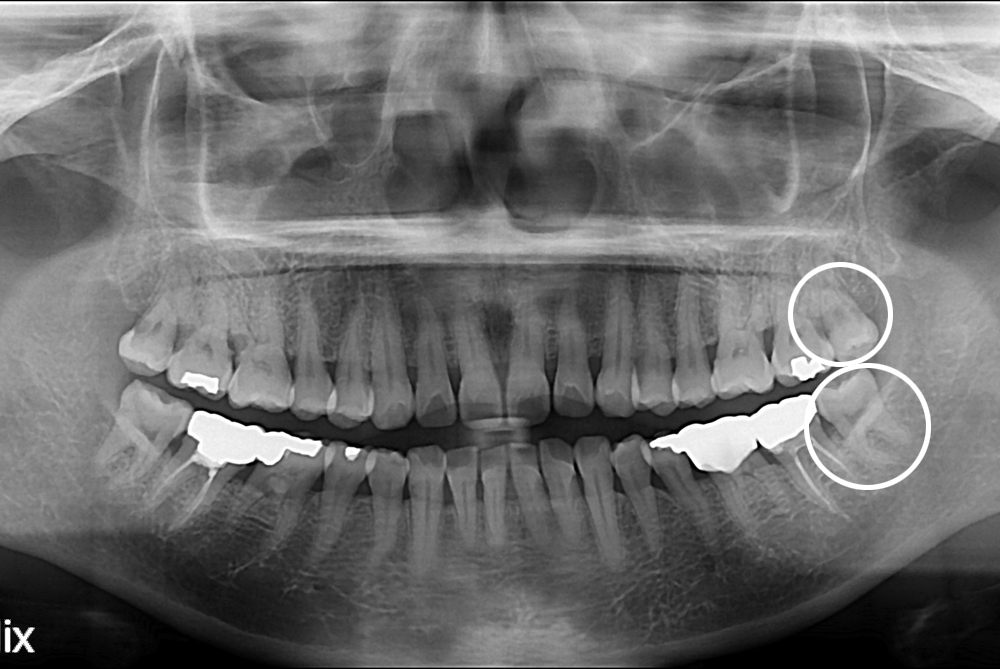

[사랑니] 난발치 사랑니 발치

치료전 : 2017-08-22

세종치과는 구강악안면외과학 박사이신 원장님이 발치하는 치과입니다.